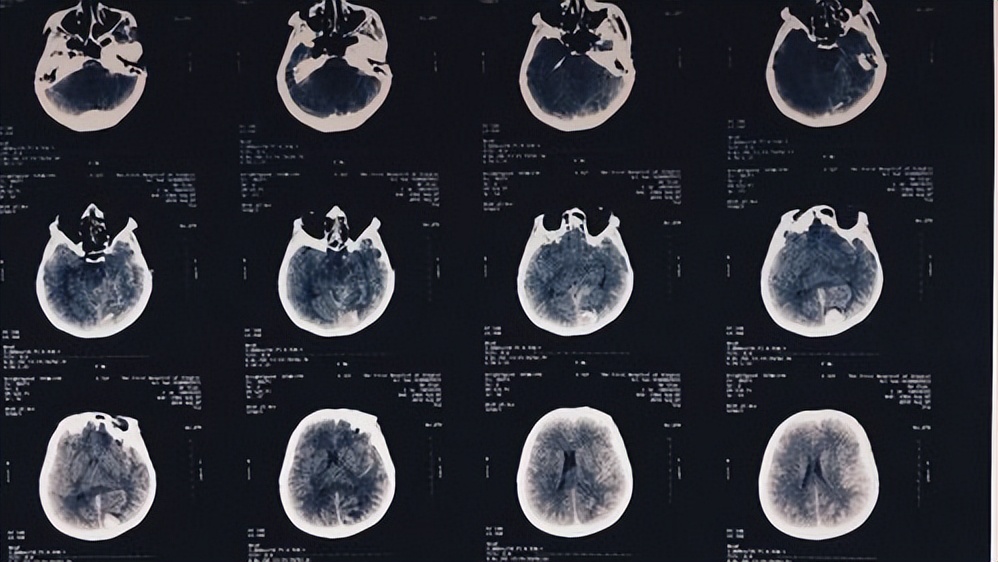

通过减少粘连性蛛网膜下腔炎和硬膜外纤维化对腰椎间盘术后的不良影响,希望能获得更好的临床治疗效果并能达到患者的满意度。 粘连性蛛网膜下腔炎是一种发生在硬脊膜内的炎症反应,影像学诊断为马尾神经根的聚集;患者通常感到灼烧样或针刺样疼痛,疼痛的范围较广;疼痛可随行走或站立而加重。